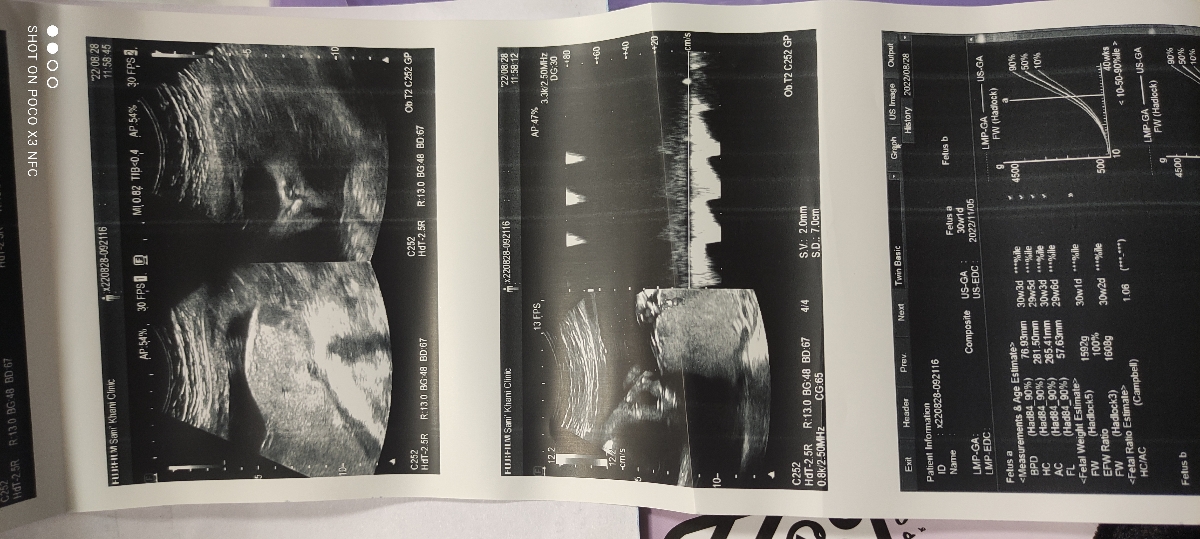

29 هفته و هفت روزم هست ،تحرکات جنین کم شده بود حجم شکمم هم کوچیک شده بود دکتر بیمارستان سونو و نوار قلب نوشتن که انجام بدم.

پزشک اوما

همه چیز در سونوگرافی شما خوب است ،در تست nst عکس کمی ناواضح است نظر خود تیم پزشکی در هنگام انجام nst در این موارد اهمیت دارد چه نظری داشتند؟

تیم پزشکی nst شامل یک پرستار و یک منشی دکتر زنان و زایمان بود که

پرستار گفت خوبه قلبش مشکلی نیست

ولی منشی دکتر گفت تحرکش کمه

توی نیم ساعت دوبار تکون خورد فقط

خواهش میکنم مامان گل ، عزیزم در این موارد باید nst تکرار میشد ایرادی ندارد، شما حتما فردا nst را در بیمارستان تکرار کنید خیالمان از هر جهت راحت شود ، اما نتیجه سونوگرافی عالی است نترسید ❤️❤️